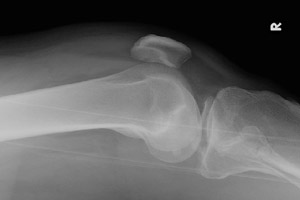

- Click on the image for a larger versionACross table lateral radiograph. This demonstrates a comminuted fracture of the tibial plateau and a fat-blood interface in the suprapatellar bursa, known as a lipohemarthrosis.